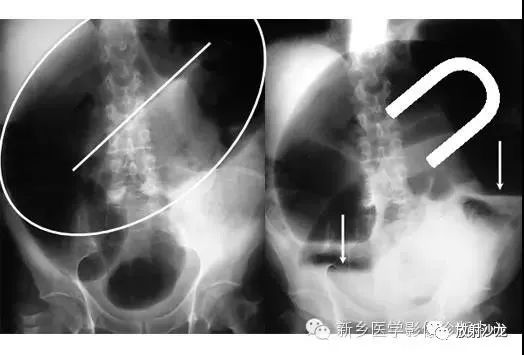

腹痛患者的腹部X光片水平位(左侧)和直立位(右侧)所上图示。是什么原因导致该病人的不适呢?

X线片表现出充满整个腹部的乙状结肠扭转。乙状结肠的两端可以理解成一个倒置的朝向骨盆的U型(图U)。在X光片直立位,可以看出气液平面(箭头)。咖啡豆的标志是乙状结肠扭转的典型的表现。充满气体的肠道包绕重叠水肿的肠壁所形成致密的白线,类似于一个咖啡豆。在这些X光片中,大肠的其余部分均不膨大,大概是因为扭转的点不造成阻塞,从而使消化产物可进入乙状结肠。

逆行通过肛管后所行X光片所示,证明了乙状结肠襻和正常肠道结构压力减低。